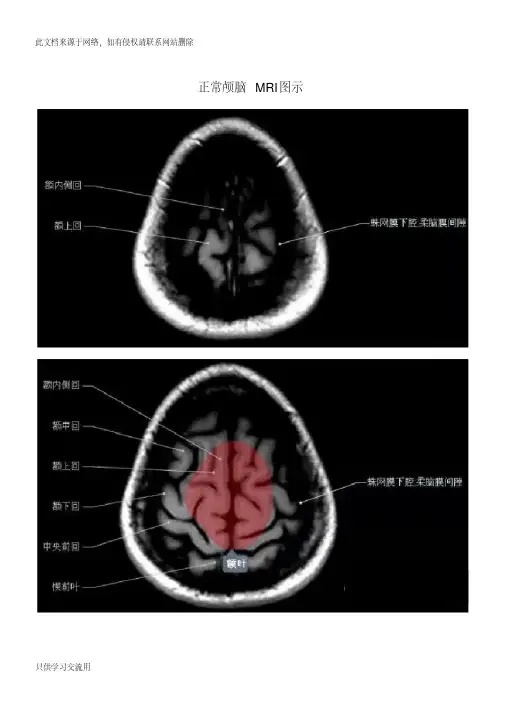

颅脑正常MRI表现阅片

颅脑的应用解剖

(一)颅骨:颅顶骨和颅底骨 (二)脑:大脑、间脑、小脑、中脑、脑桥、 和延髓 (三)脑的被膜:硬脑膜、蛛网膜、软脑膜 (四)脑室系统:侧脑室、第三脑室、第四脑 室 (五)脑的血管:脑动脉系统、脑静脉